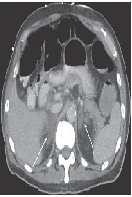

Primary Adrenal Insufficiency due to Bilateral Adrenal Hemorrhage in a Patient with Antiphospholipid Syndrome